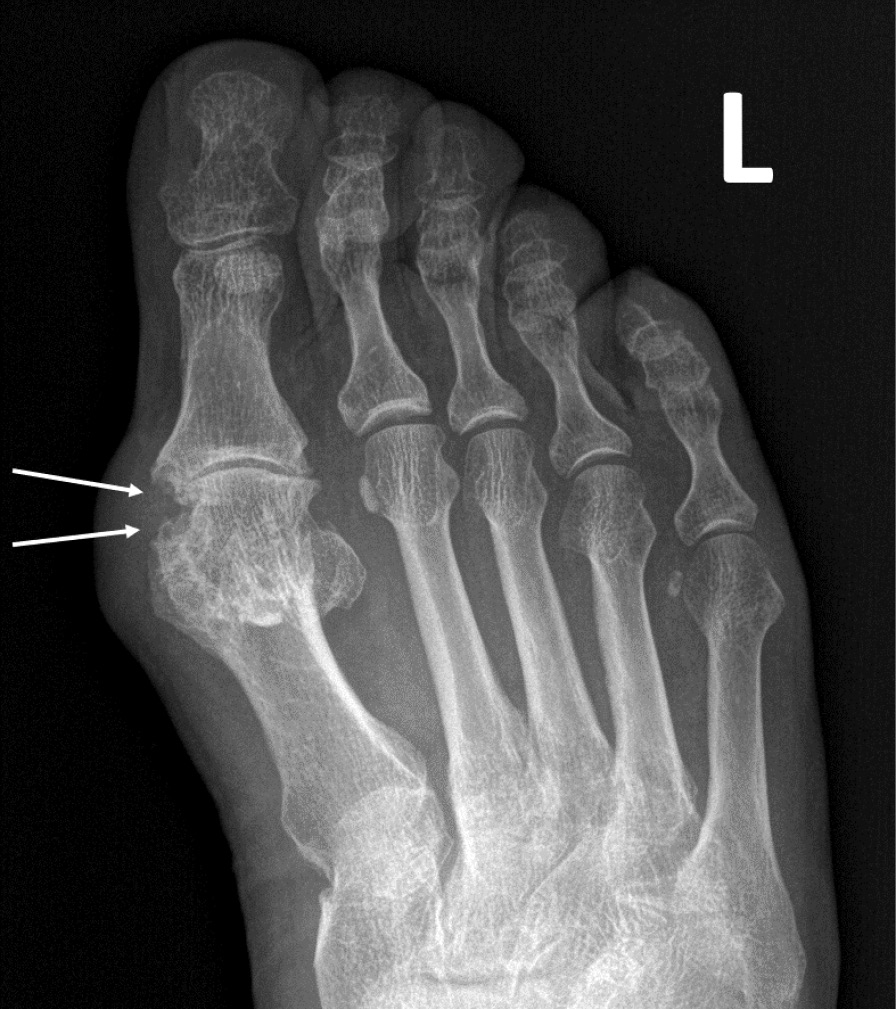

При компьютерной томографии органов грудной клетки данных за «свежие» очаговые и инфильтративные изменения не получено. Увеличения лимфатических узлов подмышечных областей, средостения, корней легких не выявлено. Отмечался усиленный грудной кифоз, обызвествление передней продольной связки, на всем уровне исследования определялись передне-боковые спондилофиты, а также анкилоз большинства реберно-поперечных суставов. По данным рентгенографии кистей (рис. 1, 2) и стоп (рис. 3, 4) диагностированы признаки эрозивного артрита, анкилоз суставов запястья. По данным МРТ крестцово-подвздошных суставов (КПС) определялся неравномерный анкилоз КПС, хрящи по суставным поверхностям неравномерной толщины, примерно на половине протяжении сустава отсутствуют, «суставной промежуток» облитерирован. Неравномерность и нечеткость контура суставных поверхностей за счет множества краевых эрозий справа, единичных – слева, с наличием остеокластоза, в нижнем отделе слева по смежным отделам определяются участки трабекулярного отека, данная находка клинически интерпретирована как двусторонний активный сакроилиит (рис. 5, 6).

Рис. 1. Рентгенограмма левой кисти в прямой проекции. Краевые эрозии суставных поверхностей первого пястно-фалангового сустава (тонкие стрелки), сужение суставных щелей суставов запястья с формированием анкилозов (толстая стрелка)

Рис. 2. Рентгенограмма правой кисти в прямой проекции. Краевая эрозия суставной поверхности лучевой кости (тонкая стрелка), множественные анкилозы суставов запястья (толстые стрелки)

В возрасте 40 лет присоединились жалобы на симметричные воспалительные боли в лучезапястных суставах и мелких суставах кистей, резкое снижение объема движения в лучезапястных суставах. При осмотре пациента выявлено: число болезненных суставов – 7, число припухших суставов – 4, положительный симптом поперечного сжатия кистей и стоп, ульнарная девиация мелких суставов стоп. Резко сниженный объем движения в лучезапястных суставах обеих кистей. По данным рентгенологического обследования зафиксированы типичные изменения для РА: резкое неравномерное выраженное сужение суставных щелей, субхондральный склероз в лучезапястных суставах, анкилоз в суставах запястья, пястно-запястных, пястно-фаланговых и межфаланговых суставах. Краевые эрозии оснований основных фаланг двух пальцев; участки кистовидной перестройки костной ткани. Локальное утолщение мягких тканей. При лабораторном обследовании пациента отмечен положительный ревматоидный фактор, высокий титр антицитруллинированных антител, повышение острофазовых белков.